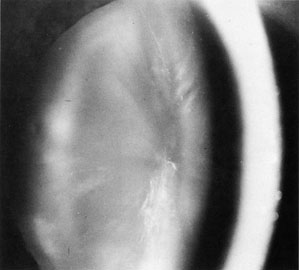

The oculocerebrorenal syndrome known as Lowe's syndrome was first described in 1952.14 It is one of the two major syndromes with naturally occurring cataracts and congenital glaucoma (the other is rubella). The cataracts are bilateral and occur in virtually all reported cases.3 They are present prior to the fifth week of development in utero, with defects of the anterior, equatorial, and posterior subcapsular areas. This is a sex-linked inherited disease. Female carriers exhibit punctate opacities of the lens, which do not cause visual impairment (Fig. 2). Glaucoma, which is present in 60% to 70% of patients, is of an infantile variety with angle anomalies. Systemic manifestations include mental retardation and renal anomalies resulting in aminoaciduria.

Fig. 2. Carrier state of Lowe's syndrome.